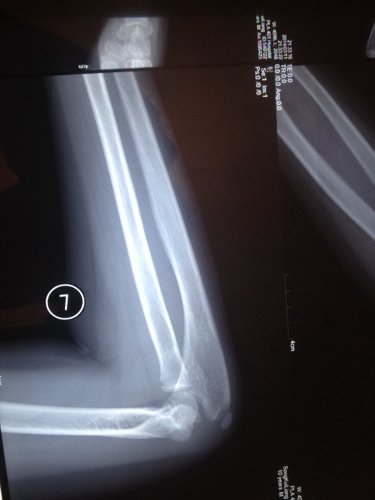

右肘玩的时候摔着了,三个蒙古的医生也没说明白是怎么回事 现在在转胳膊就痛 10岁的小孩 点击展开 匿名用户 2014-07-11 23:14 为您推荐: 其他回答 你好哦,你给宝宝做康复了吗,一般这时候是需要去做一下康复的呢,这样是会更好一些的啊 可靠的悠闲80 2014-07-12 17:41 相关问题 小孩6个多月,抱小孩时胳膊响了一下,孩子就哭个不停,响的那个胳膊就一直不动,请问医生是不是脱臼了 怎么感觉第二张图片上面,那个小孩的胳膊上面怎么好像长了个手指啊,当时检查的时候医生没说什么,今天回 请怎医生我家小孩胳膊上怎么会农了